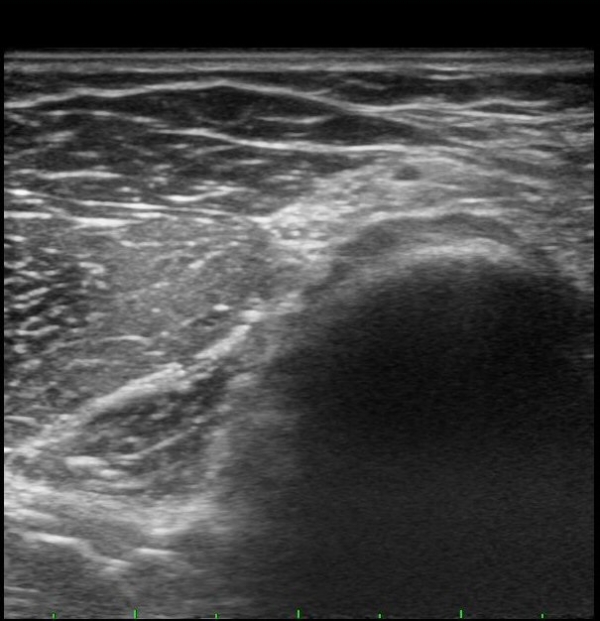

ÆÈ²ÞÄ¡ ¾ÕÂÊ È¾´Ü¸é°Ë»ç¿¡¼­ Èİñ°£½Å°æ(PIN)ÀÌ ¿ä°ñµÎ Àü¹æ¿¡¼­  Á¤»óÀûÀ¸·Î °üÂûµÊ(±×¸² 1).